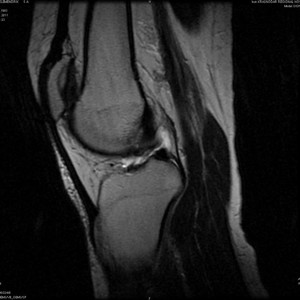

Единственным методом диагностики хондромаляции является артроскопия, которая выявляет:

МРТ показывает только тяжелые стадии патологии.

- Появление трещин, обнажения субхондральной части кости примерно в 50% суставной поверхности, склерозирование и эрозивные процессы. При 3 степени рентген и МРТ выявляет остеофиты.

- Для 4 степени характерно обширное поражение хряща более чем на 50%, атрофия мышц, боли и медиальное или латеральное смещение большеберцовой кости. На рентгене устанавливают диагноз артроз.